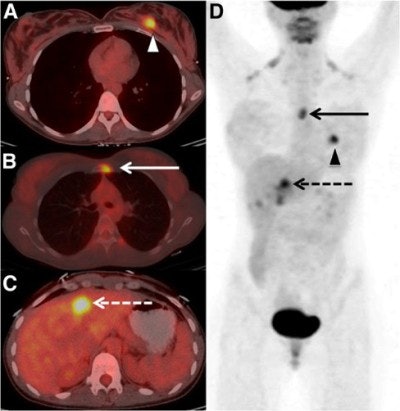

FDG-PET/CT identified unexpected extra-axillary regional nodal and distant metastases in 28 (21%) of the 134 patients. Fifteen patients (11%) had extra-axillary regional nodal metastases and 20 (15%) had distant metastases; seven patients had both regional nodal and distant metastases.

The 20 women with distant metastases were upgraded to stage IV. Sixteen patients had osseous metastases, six had distant nodal metastases, five had liver metastases, two had lung metastases, and one had a splenic metastasis. Seven patients had more than one distant metastatic site.

FDG-PET/CT upgraded to stage IV one woman out of 20 who had an initial diagnosis of stage I. In addition, two of 44 stage IIA patients, eight of 47 stage IIB patients, four of 13 stage IIIA patients, four of eight IIIB patients, and one of two stage IIIC patients were changed to stage IV.